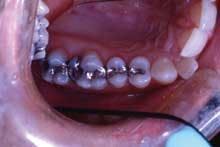

Another clinical example is this 35-year-old woman (Figure 3).

Tooth No. 19 has a large amalgam and fractures present in the lingual groove and the distal marginal ridge. Tooth No. 20 has a conservative amalgam restoration with a small area of recurrent decay present under the distal margin. When presenting the treatment plan to the patient, she is shown this picture. We explain to her the reasons we are recommending a crown with a build-up on tooth No. 19 and that the presence of the existing fracture lines put the distal lingual cusp at risk. We also explain to the patient that tooth No. 20 will require a new composite filling to replace the old amalgam restoration that is beginning to fail. We then explain the benefits of doing both restorations at the same time. Her response was, "I definitely want to do both at the same time. It's too hard for me to get time off from work to come to the dentist."